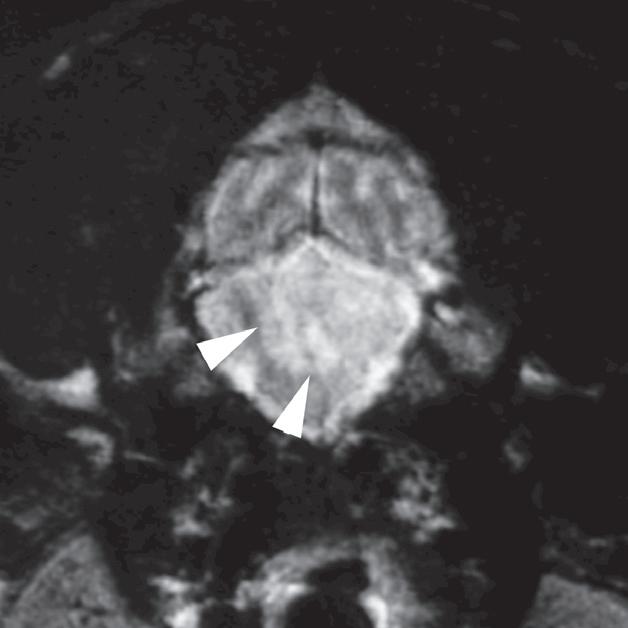

U 6-letniego samca rasy rhodesian ridgeback od 4 dni obserwowano objawy wskazujące na chorobę móżdżku. Stwierdzono słabo odgraniczony, izointensywny w T1 i hiperintensywny w T2 obszar w robaku i lewej półkuli móżdżku (a, b – groty strzałek), któremu nie towarzyszył żaden znaczący efekt masy. Po podaniu kontrastu nie zobrazowano wzmocnienia zmiany. Test immunofluorescencji pośredniej (IFA) wykazał miano zgodne z aktywnym zakażeniem Neospora. Badanie pośmiertne wykonane ok. 3 miesięcy po wstępnym rozpoznaniu potwierdziło martwicze, ziarniniakowe zapalenie móżdżku z pierwotniakami odpowiadającymi Neospora wewnątrz ognisk